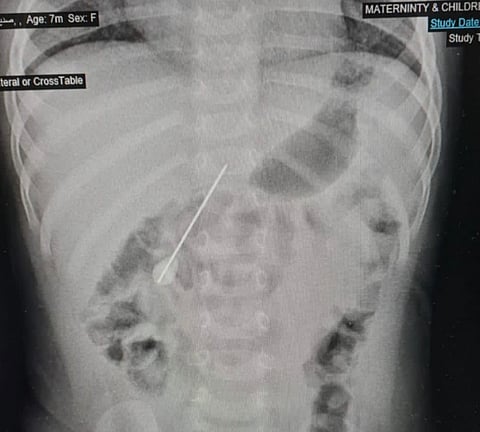

وفي التفاصيل، وصلت الرضيعة لقسم الطوارئ بالمستشفى وهي في حالة بكاء مفاجئ لا يعلم ذووها سببه، وبعد معاينة الحالة وعمل الفحوصات اللازمة لها؛ تَبين وجود إبرة كبيرة الحجم يبلغ طولها 5 سم ونصف استقرت في الأمعاء.

وعلى الفور شُكّل فريق طبي من أطباء جراحة الأطفال وقسم المناظير وقسم التخدير للتعامل مع الحالة وتجهيز الرضيعة لعمل المنظار دون تدخل جراحي؛ حيث تم إخراج الإبرة بالمنظار رغم صعوبة ذلك لكون الطفلة ما زالت رضيعة وحجم الإبرة كبير.

وتكللت العملية بالنجاح بفضل الله تعالى في وقت قياسي، وتم على إثرها إزالة الإبرة، والتأكد من التئام الثقب الذي كان في الأمعاء بسبب انغراس الإبرة، والذي أدى إلى تسرب بسيط في الهواء، وقد غادرت الرضيعة المستشفى وهي تتمتع بصحة جيدة ولله الحمد.